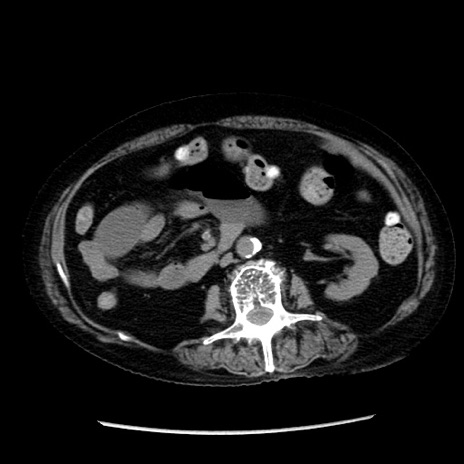

症例14(横断像)

【症例】 90歳代女性

【主訴】 腹痛・嘔吐

【現病歴】今朝から左側腹部痛を認めた。 経過観察していたが、嘔吐を認めたため来院。

【既往歴】 子宮癌術後

【身体所見】 意識清明、BP 127/54mmHg、P 98bpm Sp02 95%(RA)、BT 35.8°C、腹部平坦・軟腸ぜん動音聴取良好、右下腹部圧痛(+) 反跳痛なし

【データ】WBC 9800、CRP 0.46